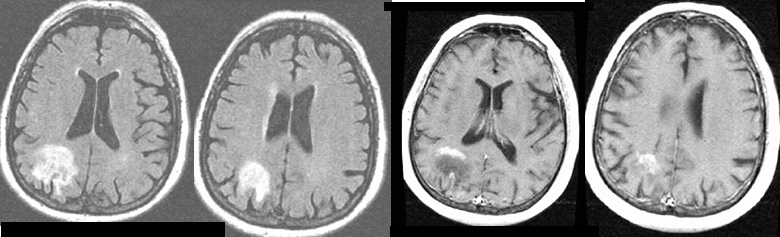

M-81 with a few months of confusion, poor memory, 2 car accidents, getting lost, misplacing items; left homonymous hemianopsia noted on exam.

Brain MRI (first 2 scans, FLAIR) shows a right parieto-occipital area of high signal from peritumoral edema, with the last two scans showing areas of gadolinium enhancement within the tumor itself